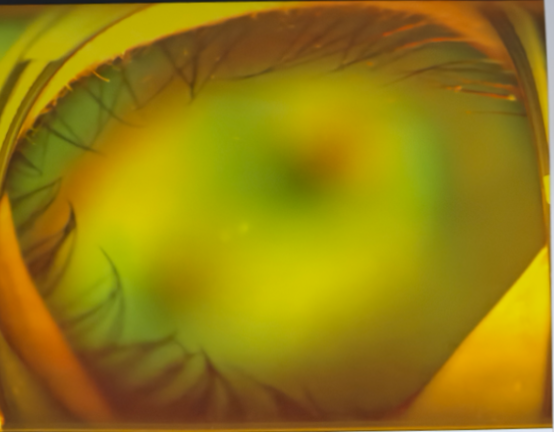

即便在眼科临床工作了50余年,见过大大小小各种疑难眼病,吴国基院长在为小宇完成全面细致的检查后,依旧难掩神情中的凝重。检查结果显示:小宇双眼确诊视网膜脱离并发白内障,其中右眼眼球已严重萎缩,视力永久丧失;左眼网脱已累及黄斑区,病情也不容乐观。